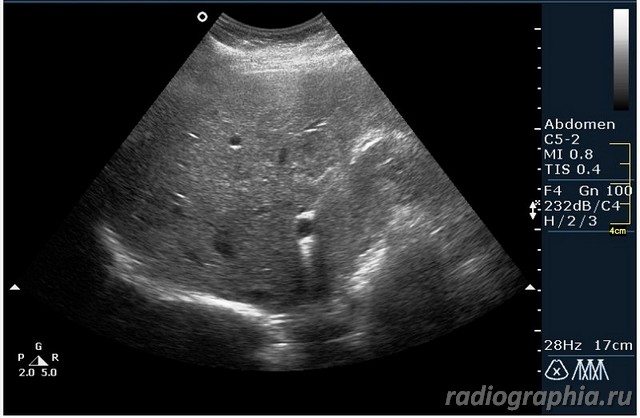

УЗИ печени. Женщина 37 лет. Жалобы на боли в эпигастрии; в печени обнаружено такое образование...

Считаю,что это опухоль,имеет неоднородную структуру,четкий контур,прорастает в сосуд(есть один такой скан) И,вообще,вся поверхность печени НЕСПОКОЙНАЯ,могут быть мелкие МТ.Интересно,что на КТ?

так и хочется назвать это метастазами но уж очень они красивые и доброжелательние по структуре (изоехогенные по отношению к структуре печени) и они больше компресирують чем проростают, склонен к ответу о доброкачественной гиперплазии. так что же на КТ?

Спсибо,но...вся печень какая-то неоднородная.